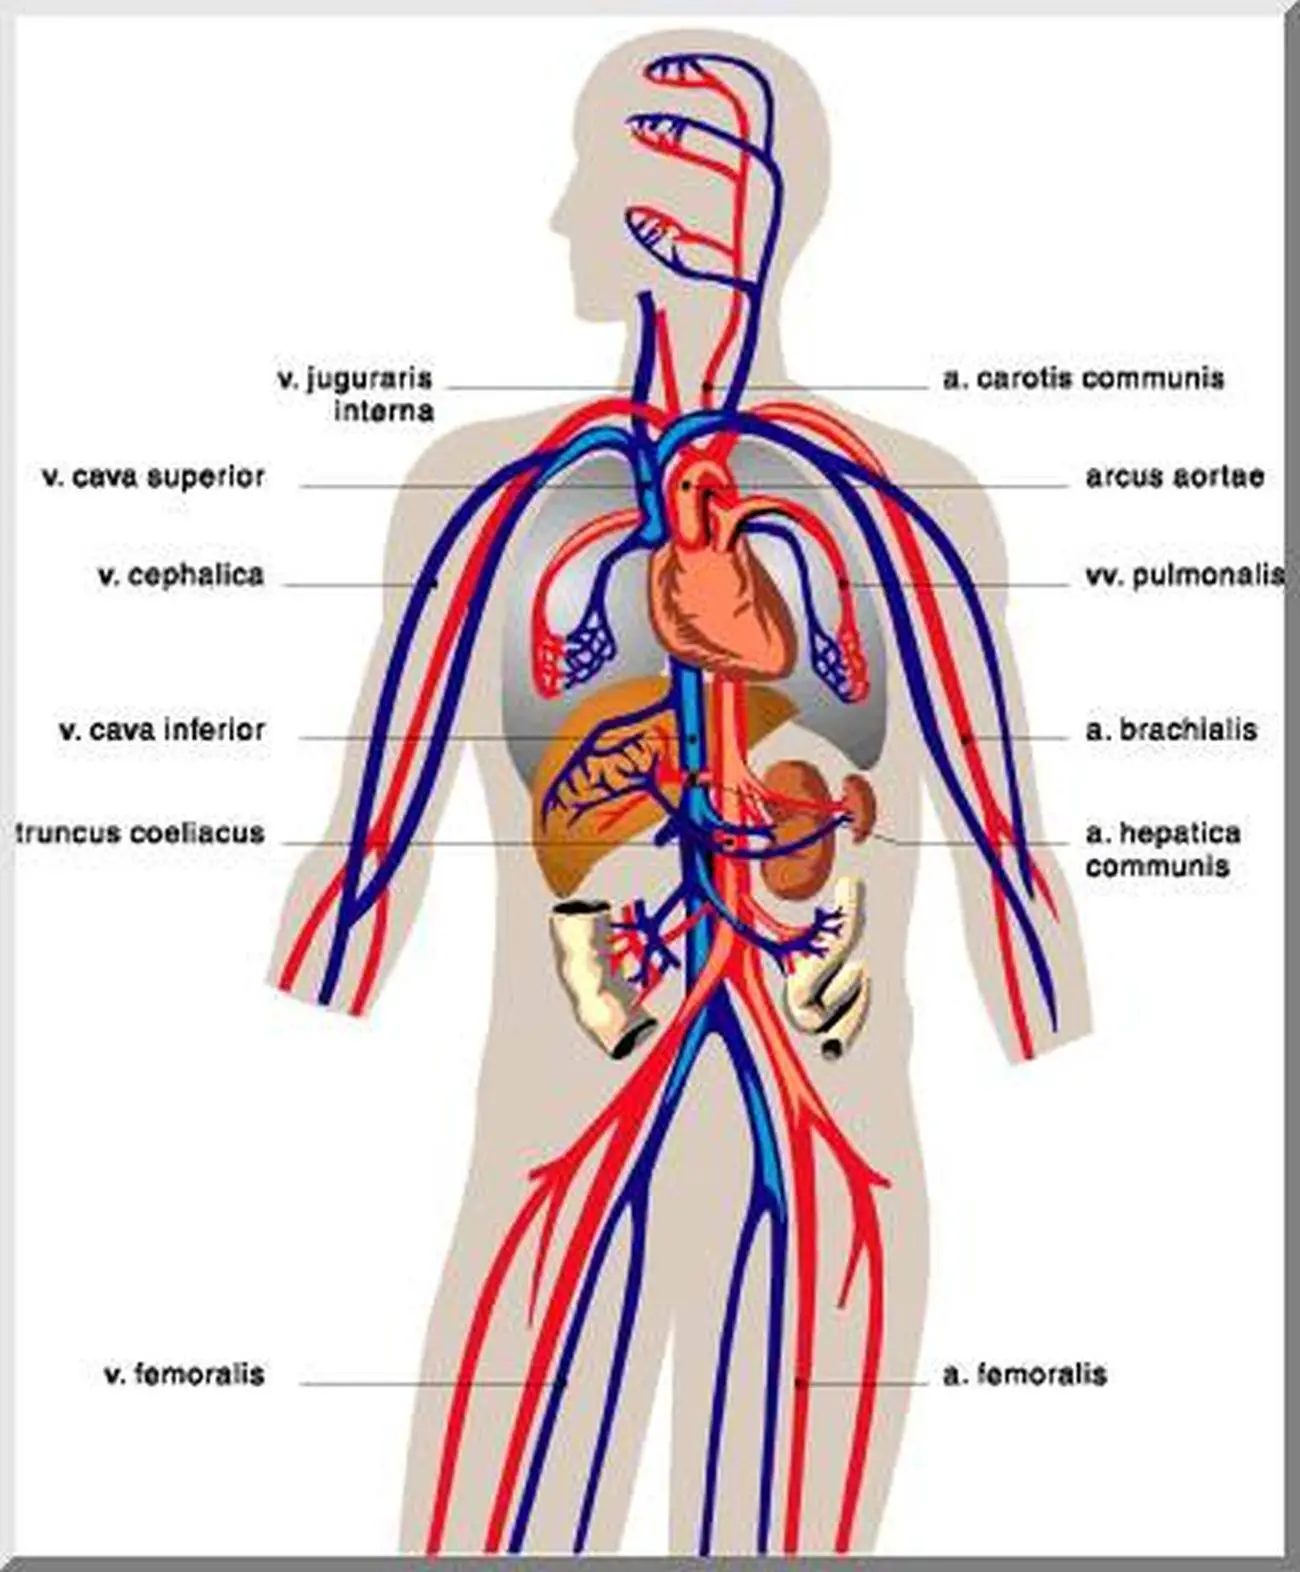

Анатомия человека: кровеносная система и её связь со скелетом